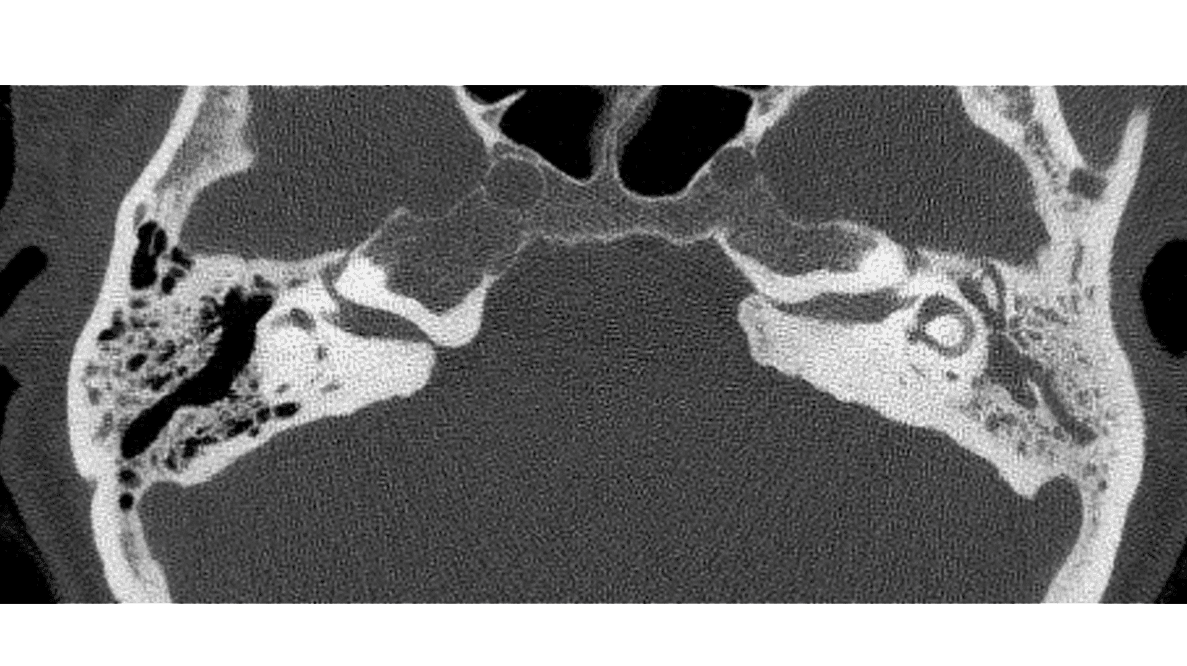

VidenskabVidenskabelig lederØre-næse-hals-specialet i fokus13. okt. 20252 min.StatusartikelAnsigtstraumer i øre-næse-hals-specialet13. okt. 20259 min.StatusartikelImplanterbare høreapparater13. okt. 202511 min.StatusartikelOtitis media13. okt. 202511 min.StatusartikelKirurgisk behandling af hyperparatyroidisme13. okt. 202512 min.StatusartikelSkæv næseskillevæg13. okt. 202511 min.StatusartikelHoved-hals-cancer13. okt. 202512 min.StatusartikelAkutte og kroniske næsebihulebetændelser13. okt. 202511 min.StatusartikelMedfødt hørenedsættelse hos børn13. okt. 202512 min.StatusartikelAkut vestibulær svimmelhed13. okt. 202511 min.StatusartikelHalsabscesser hos børn13. okt. 202511 min.StatusartikelDe hyppigst forekomne sygdomme i balanceorganerne13. okt. 202512 min.

Øre-næse-hals artikler fra Ugeskrift for Læger 20/2025StatusartikelBenigne spytkirteltumorer13. okt. 202512 min.KasuistikIdiopatisk bilateral vestibulopati13. okt. 20255 min.Ugens billedeUspecifikke halssmerter7. jul. 20252 min.KasuistikEksostose ved den indre øregang2. jun. 20254 min.KasuistikKraftig blødning efter biopsi fra nasofaryngealt juvenilt angiofibrom14. jul. 20255 min.StatusartikelNye behandlingsmuligheder for kronisk hoste6. okt. 202513 min.